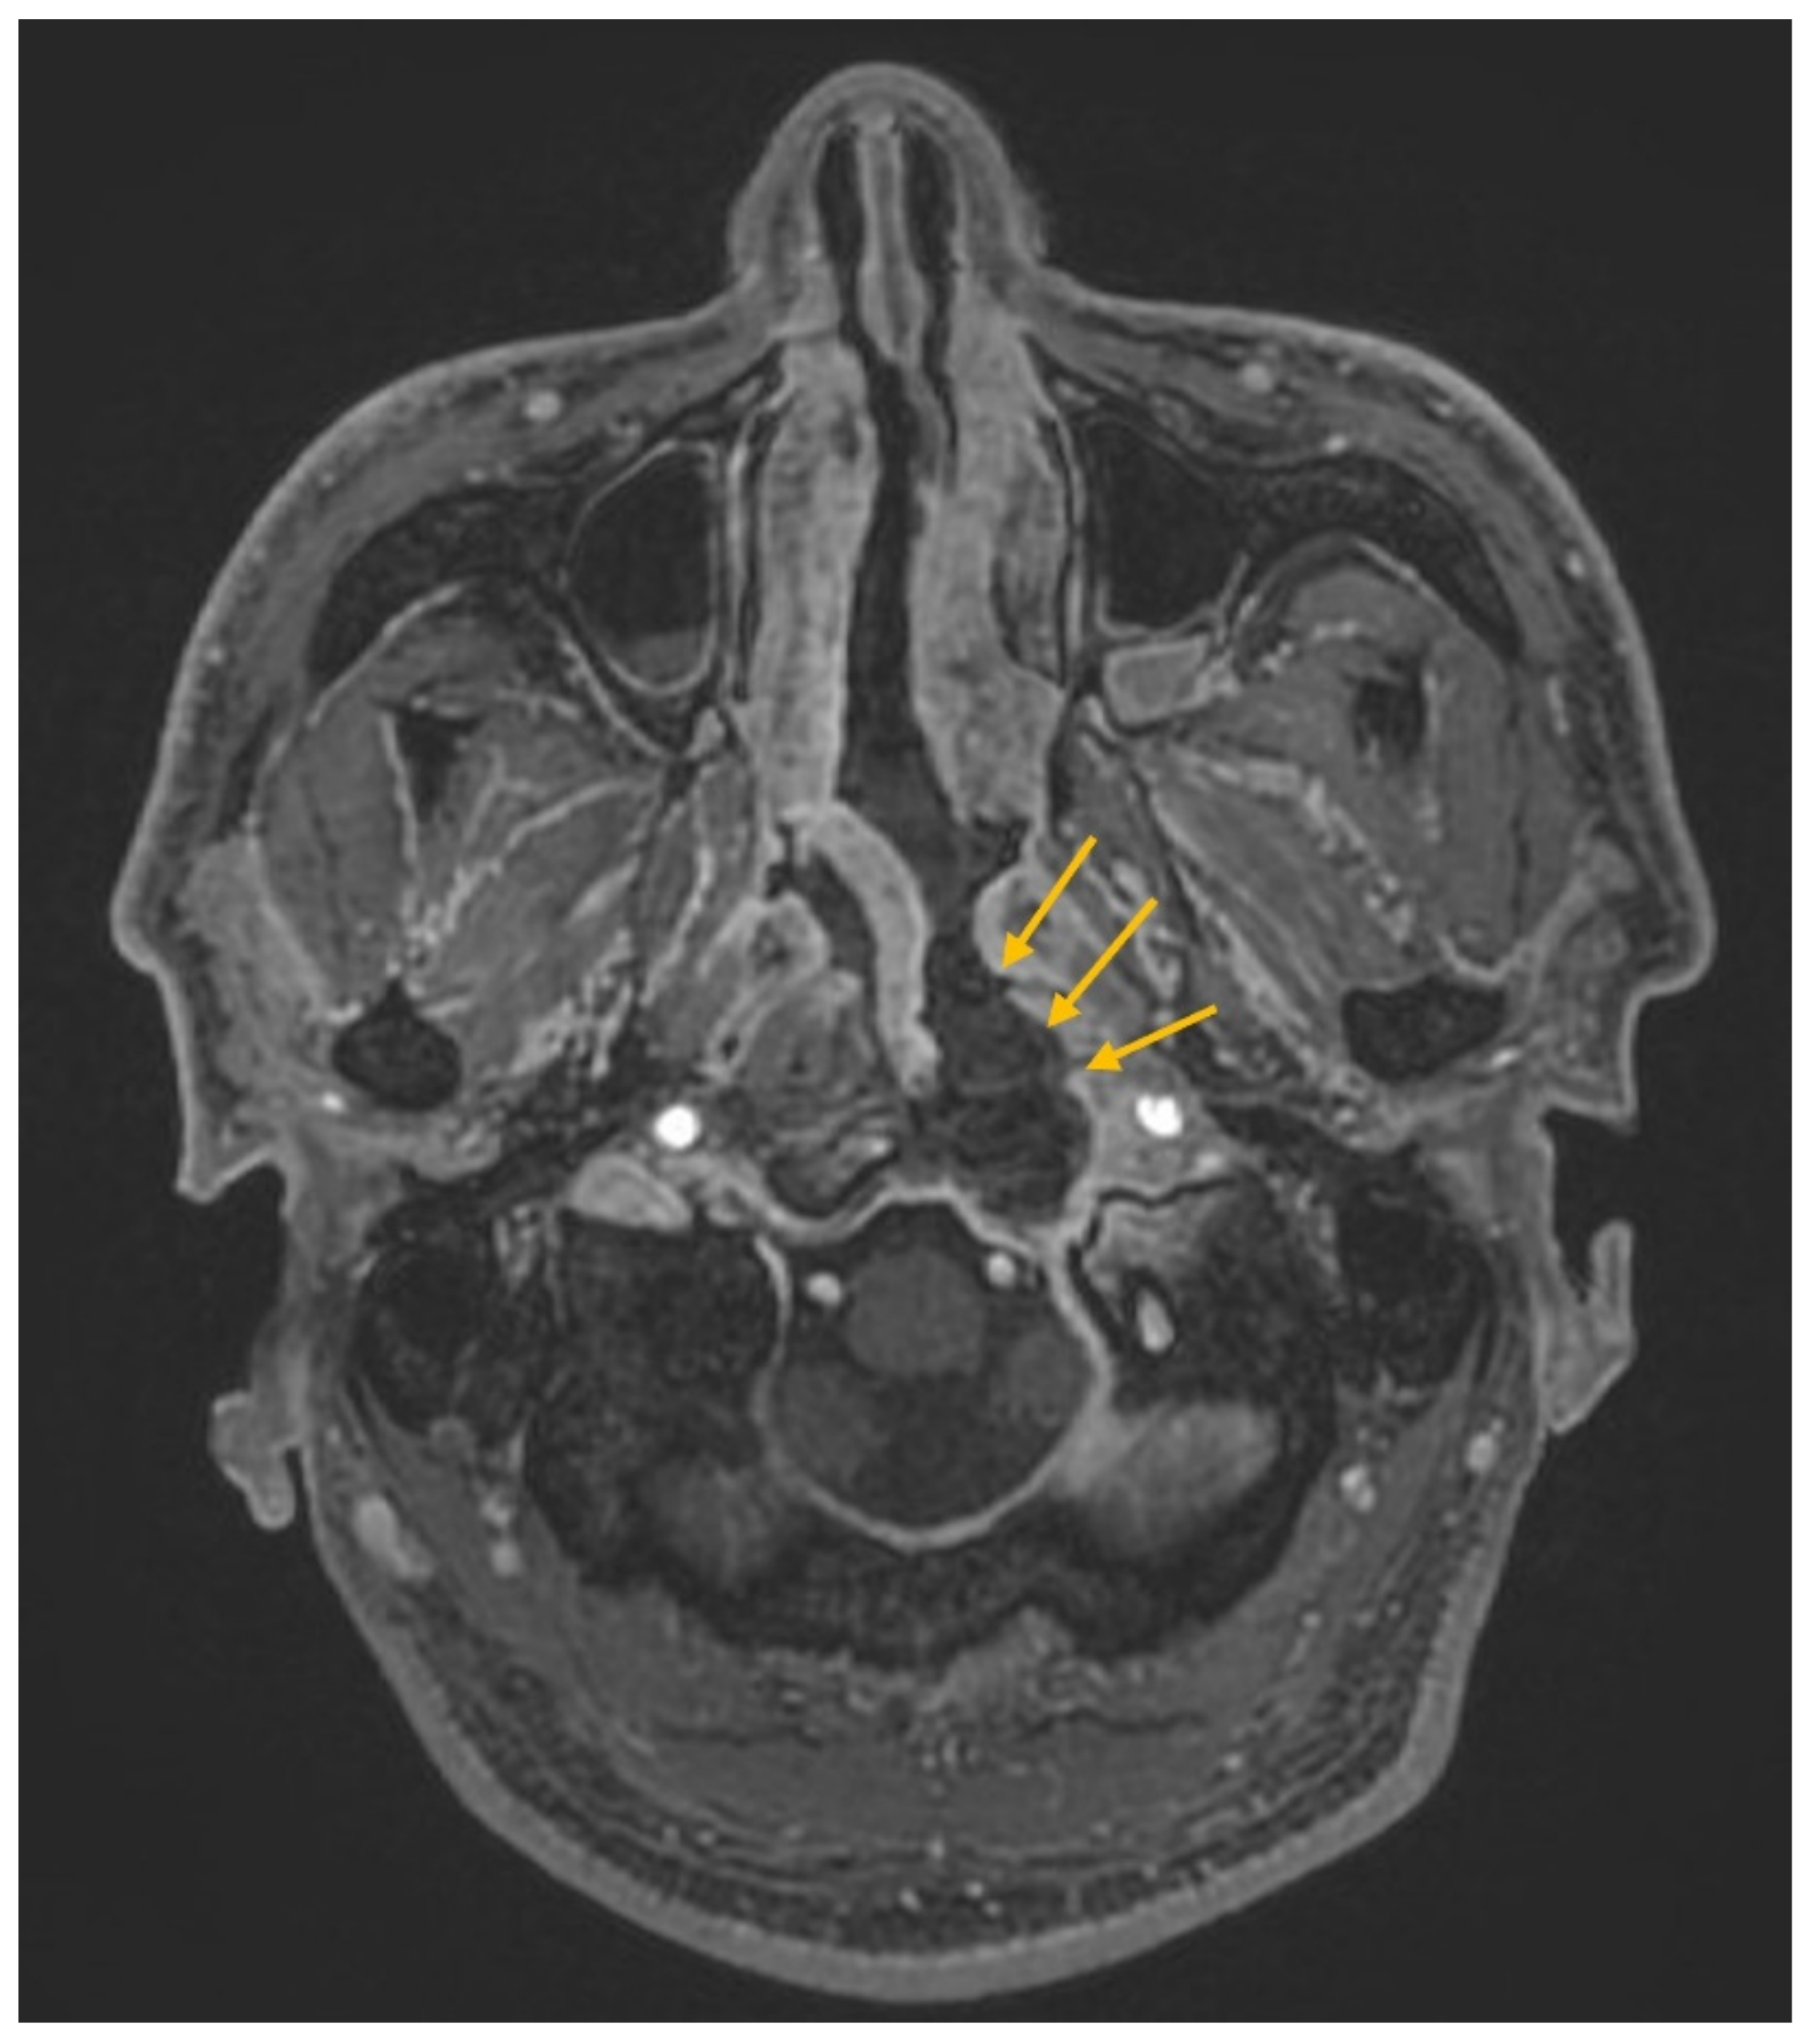

| Present case | Huang et al. | 48M | Dysphagia, hoarseness, tongue atrophy | JF, Clivus, HC, CA | IX, X, XII | T1 iso T2 hypo | + | nil | Endoscopic decompression surgery + prednisolone (10 mg/day for 100 days, oral) | 3 y |